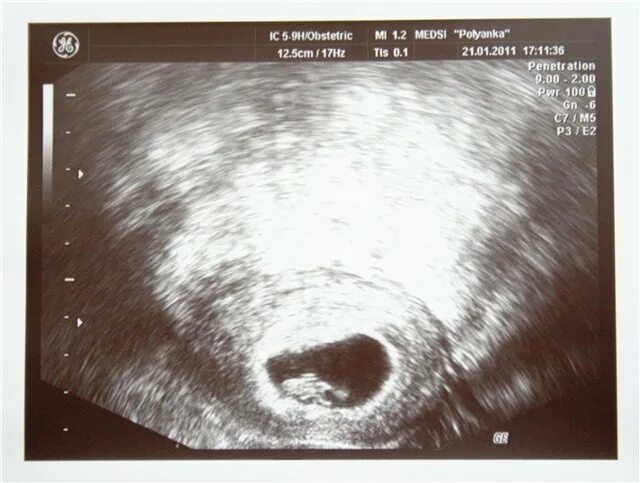

Плодное яйцо желточный мешочек